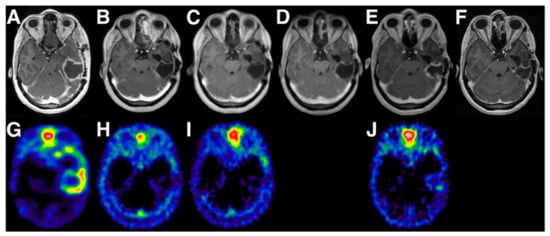

Among all diagnostic PET tracers, the most widely studied and used is [18F]-2-fluoro-2-deoxy-D-glucose ([18F]FDG). As an analog of glucose, [18F]FDG is taken up into cells by physiological glucose transport, after which it is phosphorylated to [18F]FDG-6-phosphate. Being slightly different from glucose, the phosphorylated product (FDG-6-P) is not metabolized further and remains trapped in the cell [21]. Increased cellular metabolism (i.e., glucose uptake and phosphorylation) is the underlying mechanism of higher SUVs of [18F]FDG in cancer cells compared to healthy tissue (i.e., Warburg effect) [21,22]. However, in particular in neuro-oncology studies, optimization of the TBR (i.e., contrast) is challenging because of the high physiological uptake of [18F]FDG in normal active brain tissue. To reduce uptake in healthy brain, complete fasting for a minimum of 6 h before the scan is recommended, and patients should be kept blindfolded in a quiet room during the uptake phase, or scanning times should be delayed [23]. With applying these procedures, [18F]FDG has shown acceptable sensitivity for the identification of anaplastic abnormalities in patients with low-grade glioma (LGG), high-grade glioma (HGG; Figure 1a [24]), CNS lymphoma, brain metastases, and meningioma [25,26,27]. Moreover, higher [18F]FDG uptake has shown a positive correlation with higher histologic grade and worse prognosis [26,28], making [18F]FDG PET a suitable tool for the prediction of progression-free survival (PFS) and overall survival (OS) [29]. [18F]FDG PET has shown not to be suited for radiation treatment planning, since the region of increased uptake generally covers a smaller volume than what was defined as malignant on T1-weighted gadolinium and T2-weighted MR-images [30]. In addition, [18F]FDG cannot distinguish between radiation-induced necrosis, changes in the tissue due to surgery, inflammation, or (remnant/recurrent) disease, making [18F]FDG not valuable for follow-up studies of CNS tumor therapies [21,22].

Figure 1.

Contrast-enhanced Magnetic Resonance Imaging (MRI) (top row) and multiple PET tracers for diagnostic imaging (bottom row) in glioblastoma. (a) [18F]-2-fluoro-2-deoxy-D-glucose ([18F]FDG), (b) O-(2-[18F]-fluoroethyl)-L-tyrosine ([18F]FET), (c) [18F]Fluorocholine, (d) 1-(2-Nitro-imidazolyl)-3-[18F]fluoro-2-propanol ([18F]FMISO), (e) 3′-deoxy-3′-[18F]fluorothymidine ([18F]FLT). Adapted from [24]. This research was originally published in Glioblastoma [internet]. Bolcaen, J.; Acou, M.; Descamps, B.; Kersemans, K.; Deblaere, K.; Vanhove, C.; Goethals, I. PET for therapy response assessment in glioblastoma. In Glioblastoma [Internet]; De Vleeschouwer, S., Ed.; Codon Publications: Brisbane, AU, 2017.